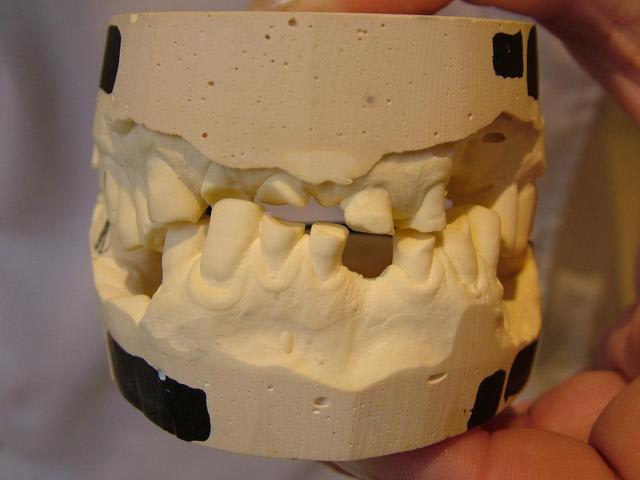

en prenant les modèles en main, je m'aperçois que le patient excerce un bruxisme important entre face distale de 34 et face mésiale de 25. Autre bruxisme important ezntre 41 et 21 et aussi entre 32 et 22. Pour ma part malgré ce sentiment d'absence de perte de DV, je ne pourrai pas reconstruire une courbe et plan correct. Qu'en penses-tu ?

Je joins les photos des modèles avec l'occlusion que le patient semble donner.